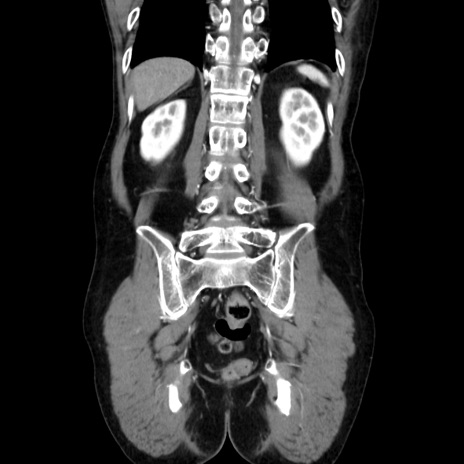

症例37(冠状断像)

横断像

【症例】40歳代 男性

【主訴】腹痛

【現病歴】4時間ほど前に電車に乗車中に臍部上より腹痛出現。徐々に増悪し起立困難となり、救急外来受診。生ものは数日食べていない。今朝お雑煮を食べた。

【身体所見】BT 36.8℃、BP 117/84mmHg、HR 91/min、SpO2 97%、苦悶様、腹部:臍上部広範囲圧痛あり、反跳痛±

【データ】WBC 8100、CRP 0.03